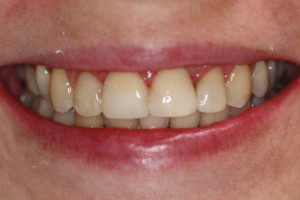

Młoda pacjentka zgłosiła się do naszego gabinetu celem wykonania kompleksowego leczenia zachowawczo-ortodontycznego. Oprócz problemów natury ortodontycznej stwierdzono złą higienę jamy ustnej oraz liczne potrzeby leczenia zachowawczo-endodontycznego. Po wnikliwej analizie telerentgenowskiej oraz analizie modeli zadecydowano o ekstrakcji 2 zębów w łuku dolnym (kła po stronie lewej oraz pierwszego przedtrzonowca po stronie prawej). Plan leczenia obejmował ponadto zamknięcie łuku po brakujących zębach w łuku górnym. Leczenie aktywne trwało 2 lata i 8 miesięcy. W czasie jego trwania pacjentka była regularnie poddawana zabiegom higieny profesjonalnej celem eliminacji zapaleń przyzębia brzeżnego. Po leczeniu aktywnym zastosowano leczenie retencyjne w postaci retainera stałego w żuchwie oraz szyny retencyjnej w łuku górnym.